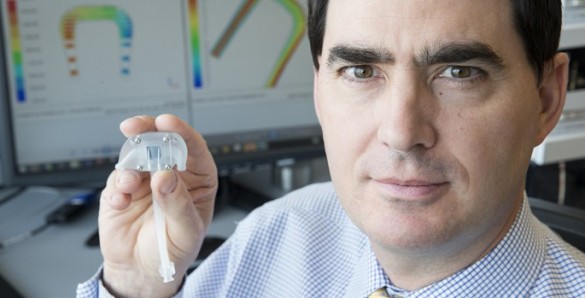

1. VU Inside: Dr. William Fissell’s Artificial Kidney

Vanderbilt University Medical Center nephrologist and Associate Professor of Medicine Dr. William H. Fissell IV is making major progress on a first-of-its-kind device to free kidney patients from dialysis. He is building an implantable artificial kidney with microchip filters and living kidney cells that will be powered by a patient’s own heart. Read more.